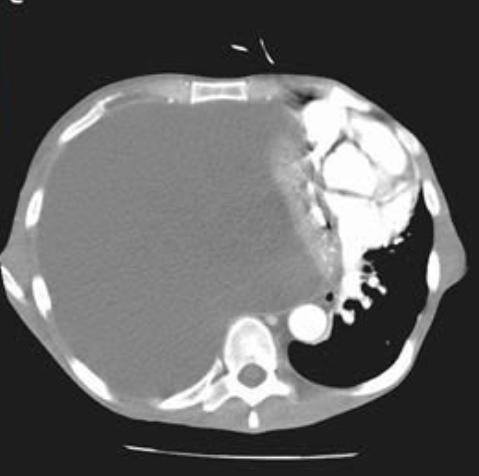

What is the diagnosis?

Cardiac tamponade

Tension hydrothorax

Diaphragmatic eventeration

Pulmonary hydatid disease

Lymphangiomyomatosis Image

Answer

Cardiac tamponade resolved after removal of 6 liters of pus from the right chest Image

A 43-year-old man

👉 respiratory distress after a 3-week illness

👉 h/o alcoholism but no other serious illness

👉 RR 34, HR 120 ,BP 80/50

👉oxygen saturation of 86% while breathing ambient air.

Read 13 tweets